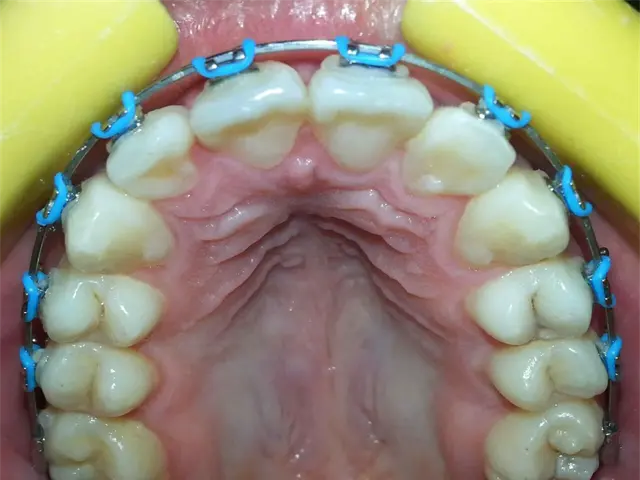

Un mal tratamiento de brackets puede llevar a provocar la pérdida de piezas dentales e incluso cambios en la estructura ósea del rostro.

Incluso señaló que un mal tratamiento de brackets puede llevar a provocar la pérdida de piezas dentales e incluso cambios en la estructura ósea del rostro.

Mencionó que es regular recibir pacientes que se dicen cansados de no notar cambios con sus antiguos médicos y al momento de revisar lo primero que se encuentra es con piezas de adorno que en ocasiones pueden llegar a ser piezas de brackets piratas.

"Cuando yo comienzo a consultar a pacientes que vienen de esos lugares me dicen que están cansados de no ver cambios, al momento de revisar me doy cuenta que faltan brackets, los que dicen brackets por 700 pesos, muchos van a cursos ya aprenden lo básico que es poner un bracket, pero para esto no tienen los conocimientos de ortodoncia, entonces el bracket no es mágico, quien hace el trabajo es el ortodoncista”, explicó.